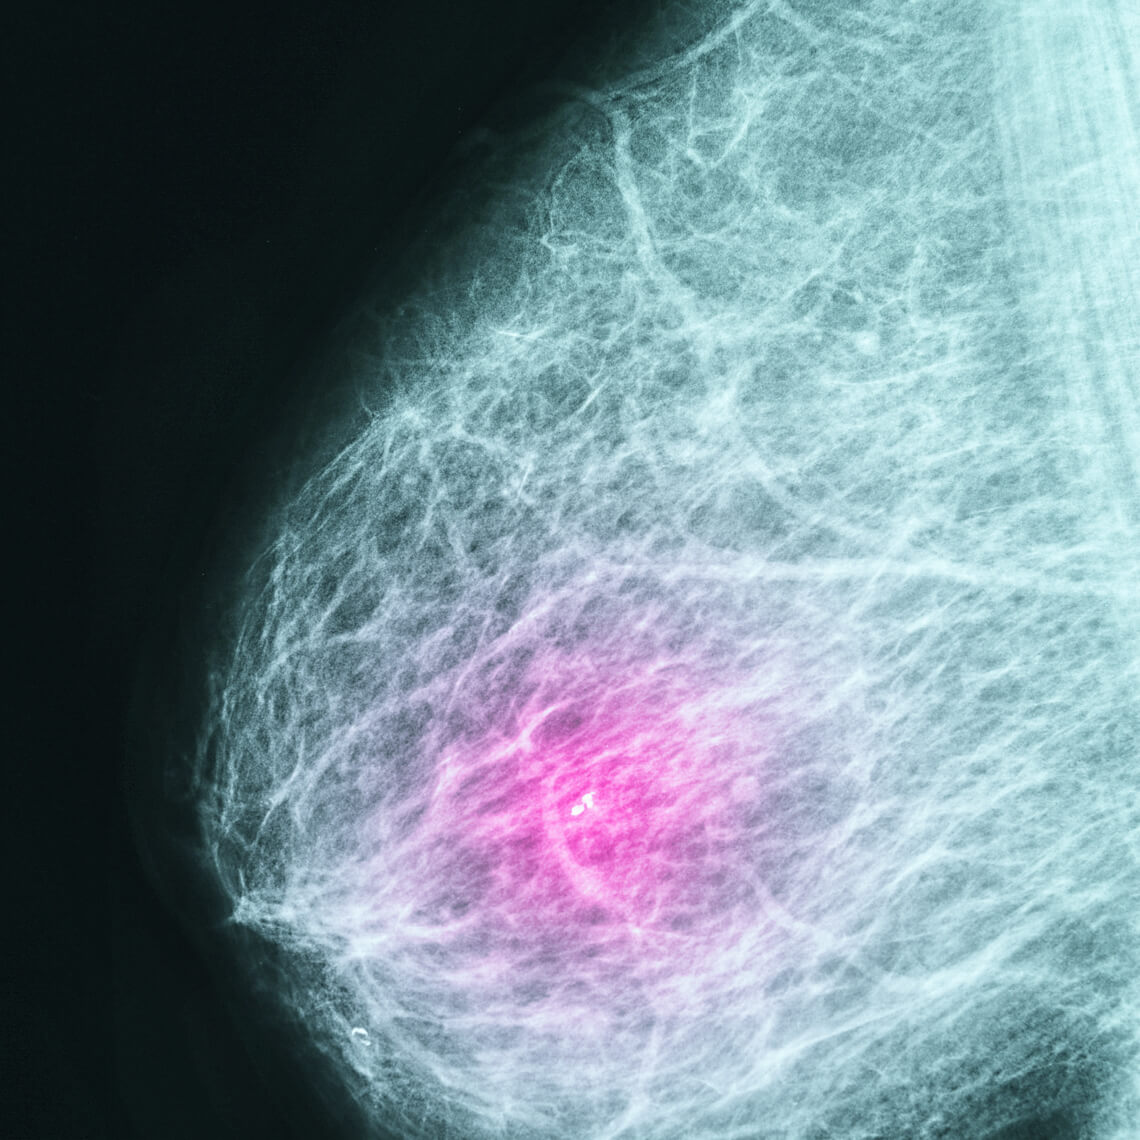

Delayed Breast Cancer Diagnosis due to Automated EHR Report Error